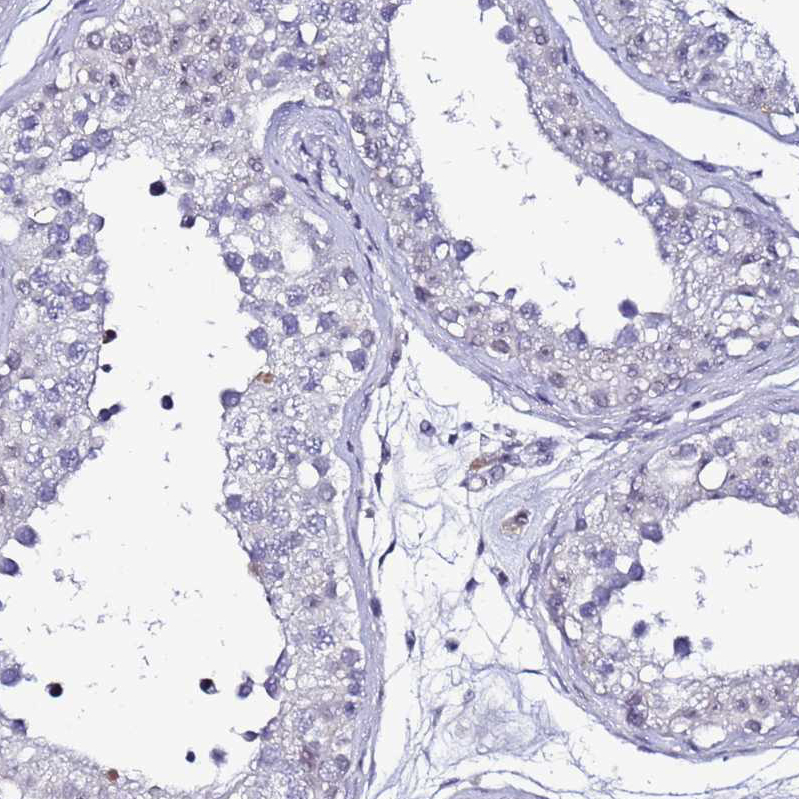

Immunohistochemical staining of human liver shows moderate nuclear positivity in hepatocytes.